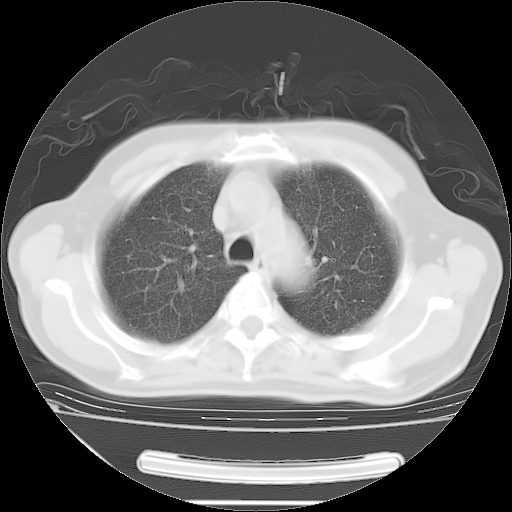

今天复查肺部CT,发现双肺广泛磨玻璃样改变。所以我把3月19日和5月9日相隔50天的肺部CT上传。请大家会诊。

2009年3月19日肺部CT片。

2009年3月19日肺部CT